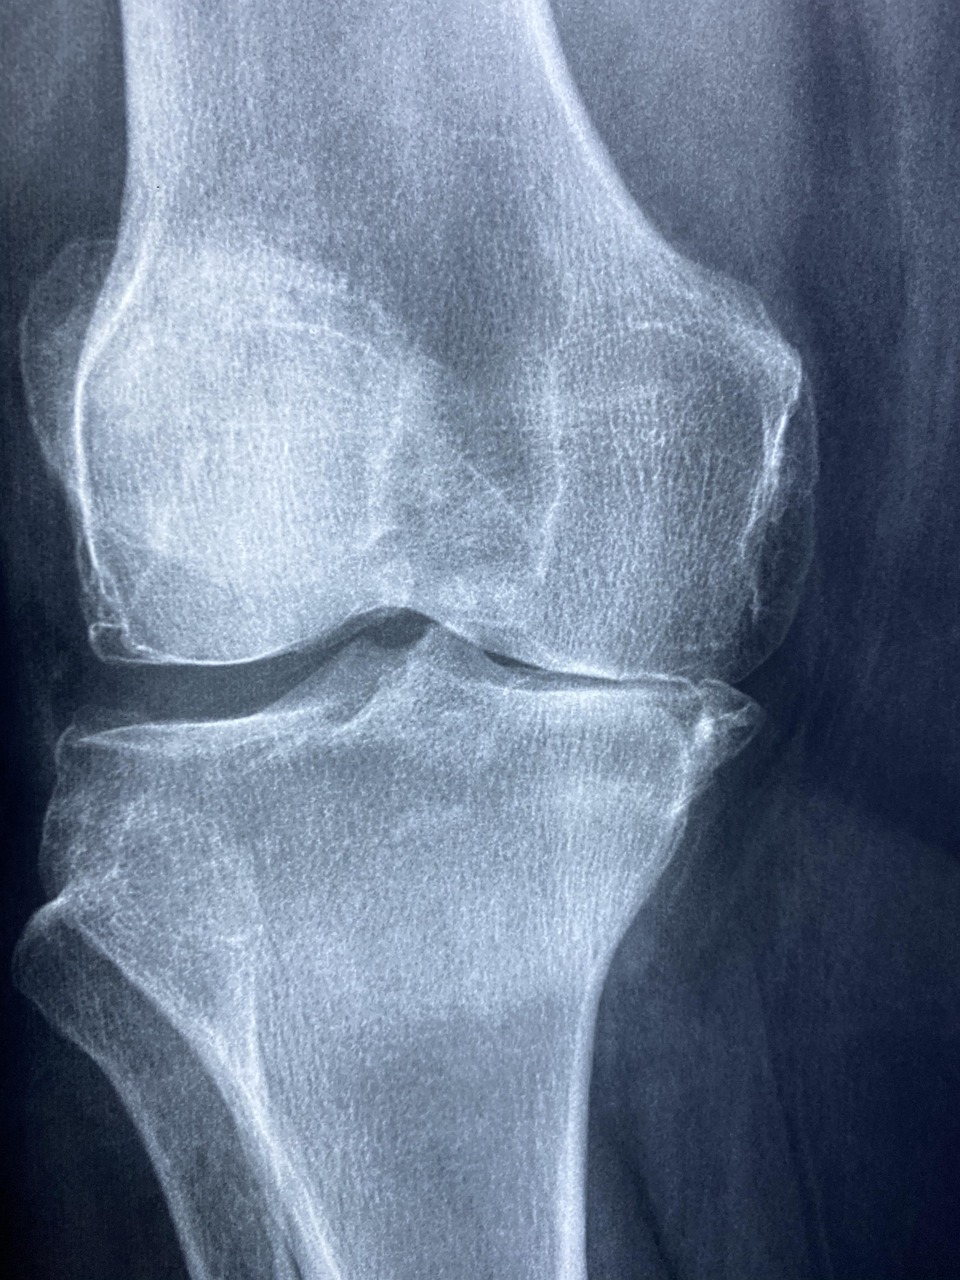

- Diagnostik mit bildgebenden Verfahren (z. B. Röntgen, MRT, Ultraschall)

Berlin verfügt über ein breites Angebot an medizinischen Fachrichtungen. Gerade bei orthopädischen Beschwerden ist es jedoch entscheidend, eine Praxis zu wählen, die Erfahrung, moderne Diagnostik und individuell zugeschnittene Therapien verbindet. Komplexe Krankheitsbilder wie Arthrose, Bandscheibenvorfälle oder Sportverletzungen erfordern oft eine Kombination aus konservativer Therapie und innovativen Behandlungsmethoden.